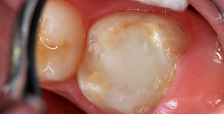

A 9-year-old presented with hypoplasia, hypocalcification, and caries.

Figure 1

A 9-year-old boy had a partially erupted mandibular first molar with much hypocalcification of the occlusal surface and a large caries lesion involving the occlusal and buccal surfaces (Figure 1). The patient complained of continuing sensitivity to cold stimulus and air inspiration. Because the tooth was only partially erupted, consideration for stainless steel crown full coverage had to be delayed. As an interim repair, it was decided to debride the carious tooth substance and place a light-hardened calcium silicate/mineral trioxide aggregate (MTA) liner, followed by a bonded restoration. After inferior alveolar block anesthetic injection and cotton roll isolation, cavity outline form was cut using a high-speed, water-cooled, medium-grit cylindrical diamond bur (Figure 2). Insufficient eruption precluded use of a rubber dam. A large, round bur at slow speed was used to debride the carious enamel and dentin. The prepared surfaces were swabbed for two 60-second applications of a 5% glutaraldehyde/HEMA solution for desensitization and disinfection of the preparation.6,7 Cavity liner was then injected and spread over the deepest sections of the cavity floor and hardened with the visible light beam (Figure 3). After a self-etching bonding agent was applied over the remaining enamel surfaces, without the need for any type of matrix, an RMGI bioactive ionic resin-based composite was injected, in one portion, into the preparation and spread over the four cusps using a ball burnisher. This restorative complex was then photo-polymerized using two 20-second exposures of the visible light beam (1,200 mW/cm2). The restoration was trimmed and finished with large, round diamond burs at slow speed, and occlusion was evaluated with articulating paper and adjusted.